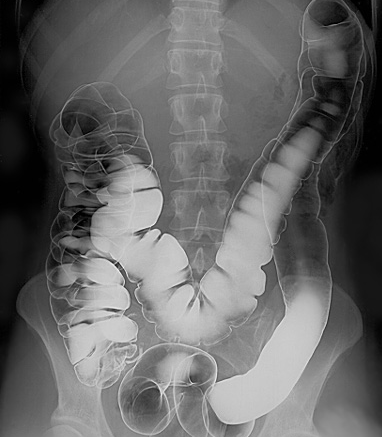

Ein Bariumeinlauf ist eine rektale Injektion von Bariumkontrastmittel. Damit wird die Schleimhaut des Dickdarms und des Enddarms beschichtet, und unter Durchleuchtungskontrolle werden Röntgenaufnahmen gemacht. Für ein Doppelkontrastverfahren kann auch Luft in den Dickdarm eingeführt werden. Aufgrund der zunehmenden Verbreitung der Koloskopie und der CT-Kolonographie werden Bariumeinläufe heute viel seltener durchgeführt als früher.

Bariumeinlauf in den Darmtrakt

By Glitzy queen00 at English Wikipedia, gemeinfrei, via Wikimedia Commons

Barium wird unter Schwerkraft in den Dickdarm geleitet, und es werden Röntgenaufnahmen gemacht. Für einen Doppelkontrast-Bariumeinlauf wird dann auch Luft in den Enddarm eingeführt.